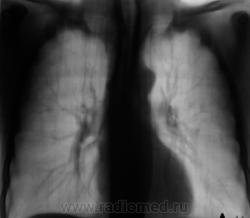

Рентгенограмма.

С двух сторон в верхних долях очаги. На вскидку tbs. А что с клиникой, анализами, анамнез.

Двусторонний очаговый туберкулез.

В s 1 -2 и глубоких отделах s6судя по срезам очаги,справа с включениями кальция,на фоне фоброзно измененного легочного рисунка

Скорее диссеминирмванный так как пораженно более 2-х сегментов.